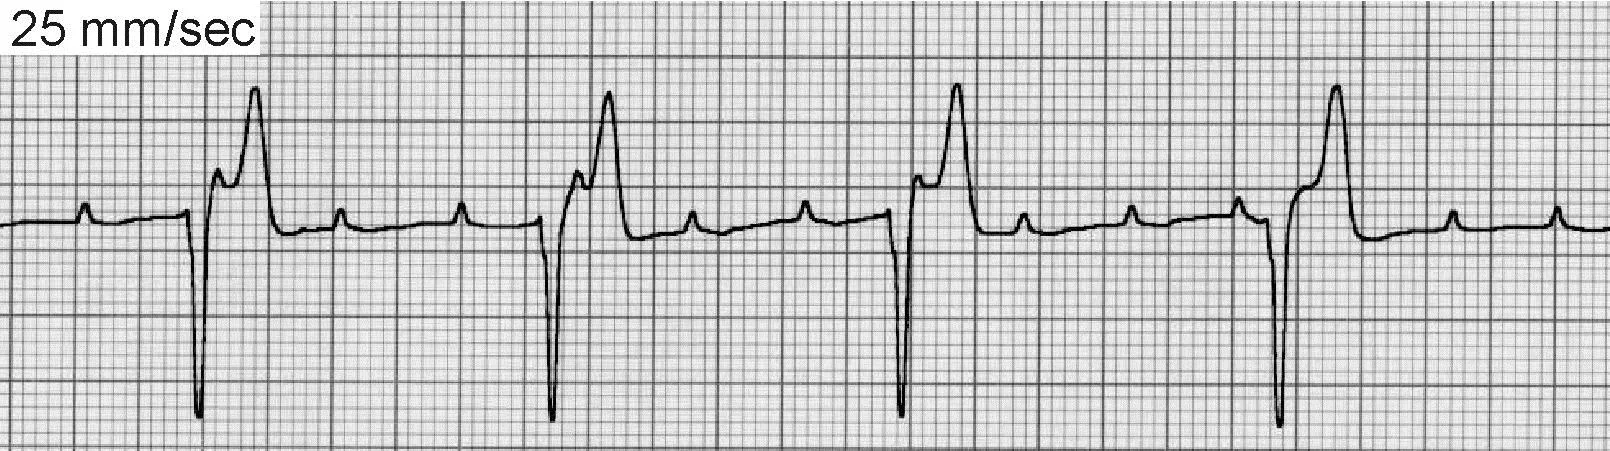

Paroxysmal VT (Figure 2B) may produce irregular bursts of tachycardia that interrupt an otherwise normal rhythm.

FIGURE 2BECG of paroxysmal ventricular tachycardia